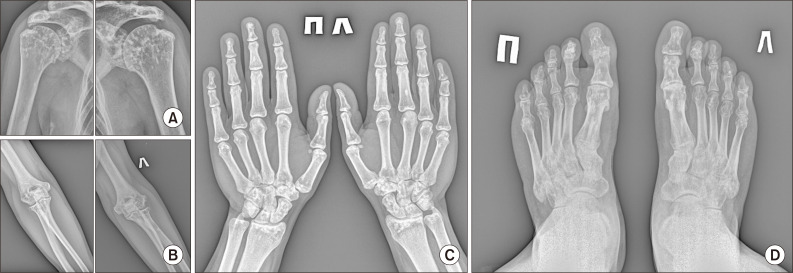

Osteopoikilosis (OPK) is a rare benign congenital genetic-mediated sclerosing skeletal disease, characterized by the formation of osteosclerosis foci. OPK is usually clinically asymptomatic, but some patients (15%~20%) may have arthralgia and synovitis. OPK may be associated with rheumatic diseases and might lead to unreasonable over-examination in real clinical practice. Single cases of the OPK together with ankylosing spondylitis (AS) have been described. Here we present a 33-year-old patient diagnosed with AS coexisting with OPK. In the case considered, the combination of AS and OPK accompanied with a high activity of inflammation, peripheral arthritis, a rapid rate of structural progression in axial skeleton, inefficiency of disease-modifying antirheumatic drugs and nonsteroidal anti-inflammatory drugs, a lack of response to anti interleukin-17 and a good response to a tumor necrosis factor inhibitor golimumab. We describe the important points of differential diagnosis associated with the identification of focal changes in bone tissue, especially neoplastic lesion. Foci revealed had typical localization, so, acquaintance of practicing doctors with such rare cases would minimize unnecessary examinations.

骨硬化症(Osteopoikilosis,OPK)是一种罕见的先天性遗传介导的良性硬化性骨骼疾病,以形成骨硬化灶为特征。OPK 通常无临床症状,但部分患者(15%~20%)可能会出现关节痛和滑膜炎。OPK 可能与风湿性疾病相关,在临床实践中可能会导致不合理的过度检查。已有单例 OPK 合并强直性脊柱炎(AS)的病例。在此,我们介绍了一名被诊断为强直性脊柱炎合并 OPK 的 33 岁患者。在该病例中,强直性脊柱炎和强直性脊柱炎合并症伴有高炎症活性、外周关节炎、轴向骨骼结构进展速度快、改善病情抗风湿药物和非甾体抗炎药物疗效不佳、对抗白介素-17缺乏反应以及对肿瘤坏死因子抑制剂戈利木单抗反应良好。我们描述了与识别骨组织病灶变化(尤其是肿瘤病变)相关的鉴别诊断要点。所发现的病灶具有典型的定位性,因此,执业医生对此类罕见病例的了解将最大限度地减少不必要的检查。